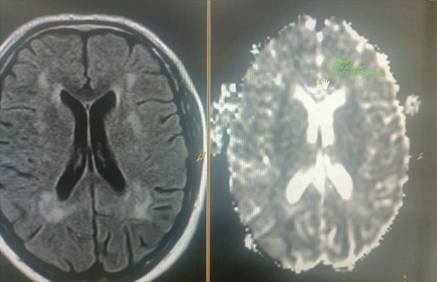

Background: Chronic Multiple Sclerosis (MS) modifies the apparent diffusion coefficient (ADC) value due to severe pathological changes. After trauma, it is the second most common cause of brain injury in healthy young adults. MRI is considered the initial imaging modality for MS diagnosis and follow-up. Objective: To assess the significance of the ADC in the diagnosis and follow-up of MS plaques across various disease subtypes. Methods: Forty MS patients were included in a case-control study at Ibn-Sina Teaching Hospital, Mosul Province, between June 1, 2022 and February 28, 2023. The patients had diffusion-weighted and traditional MR imaging with ADC measurement in plaques, and the normal white matter value of controls was compared to the patients' results. Results: The ADC values were higher in cases that were acute or secondary-progressive than in relapsing-remitting cases or normal white matter. In both types of newly generated plaques, there was an initial non-significant increase in ADC values compared to existing plaques. Overall, the ADC sensitivity, specificity, and accuracy in diagnosing MS were 85.7%, 95.2%, and 90.5% in acute cases, and 85.7%, 83.3%, and 84.6% in chronic cases, respectively, with no significant difference between active and inactive lesions. Conclusions: The apparent diffusion coefficient value can be included in the imaging protocol for the diagnosis and follow-up of various subtypes of MS.